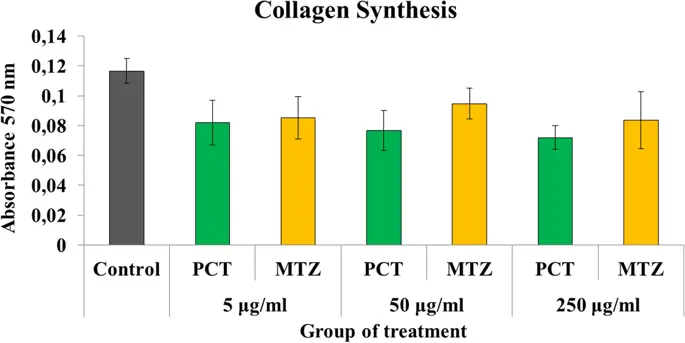

Миграция фибробластов ингибировалась в большей степени парацетамолом и метамизолом по сравнению с контрольной группой (р <0, 05) ( рис. 6 ). Ингибирование метамизола и парацетамола при миграции фибробластов было эквивалентным при дозах 5 мкг / мл (2, 34 ± 0, 29 против 2, 53 ± 0, 42 мм; р> 0, 05) и 50 мкг / мл (3, 04 ± 0, 51 против 2, 86 ± 0, 20 мм).; р> 0, 05), но эффект метамизола был выше в подавлении миграционной активности, чем парацетамол, при более высокой концентрации дозы 250 мкг / мл (1, 92 ± 1, 11 против 4, 08 ± 0, 44 мм; р <0, 05). Кроме того, парацетамол и метамизол не влияли на синтез коллагена фибробластов толстой кишки через 48 ч после операции по сравнению с контрольной группой при всех дозах лечения (р> 0, 05) ( рис. 7 ).

Средняя активность синтеза коллагена в фибробластах при различных обработках. Нет разницы между тремя группами, которые ингибируют синтез коллагена (р> 0, 05)

Активность фибробластов в синтезе коллагена будет увеличиваться на этапах заживления раны анастомоза. Однако наше исследование показало, что метамизол и парацетамол не выявили каких-либо значительных ингибирований синтеза коллагена по сравнению с контролем. Кроме того, предыдущие отчеты in vivo показали, что барьеры, вызванные метамизолом и парацетамолом для синтеза коллагена, эквивалентны контрольной группе (28, 29).